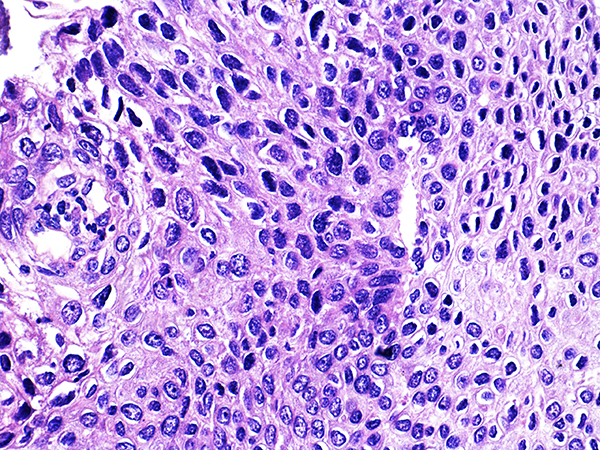

![]() Case 3

Soft Bx CIN 3

40x - High Power |